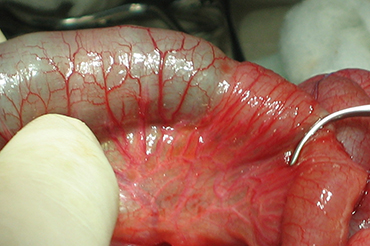

Atresia Intestinal

Inicio Neonatal y Lactante

Neo Natal y Lactante